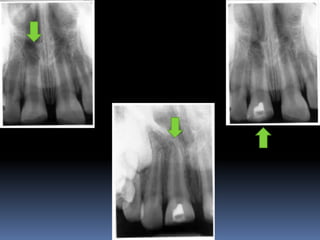

Diagnosis and assessment:

 Radio graphs

A radiolucent area usually surrounds the apex of an

immature root with a healthy pulp